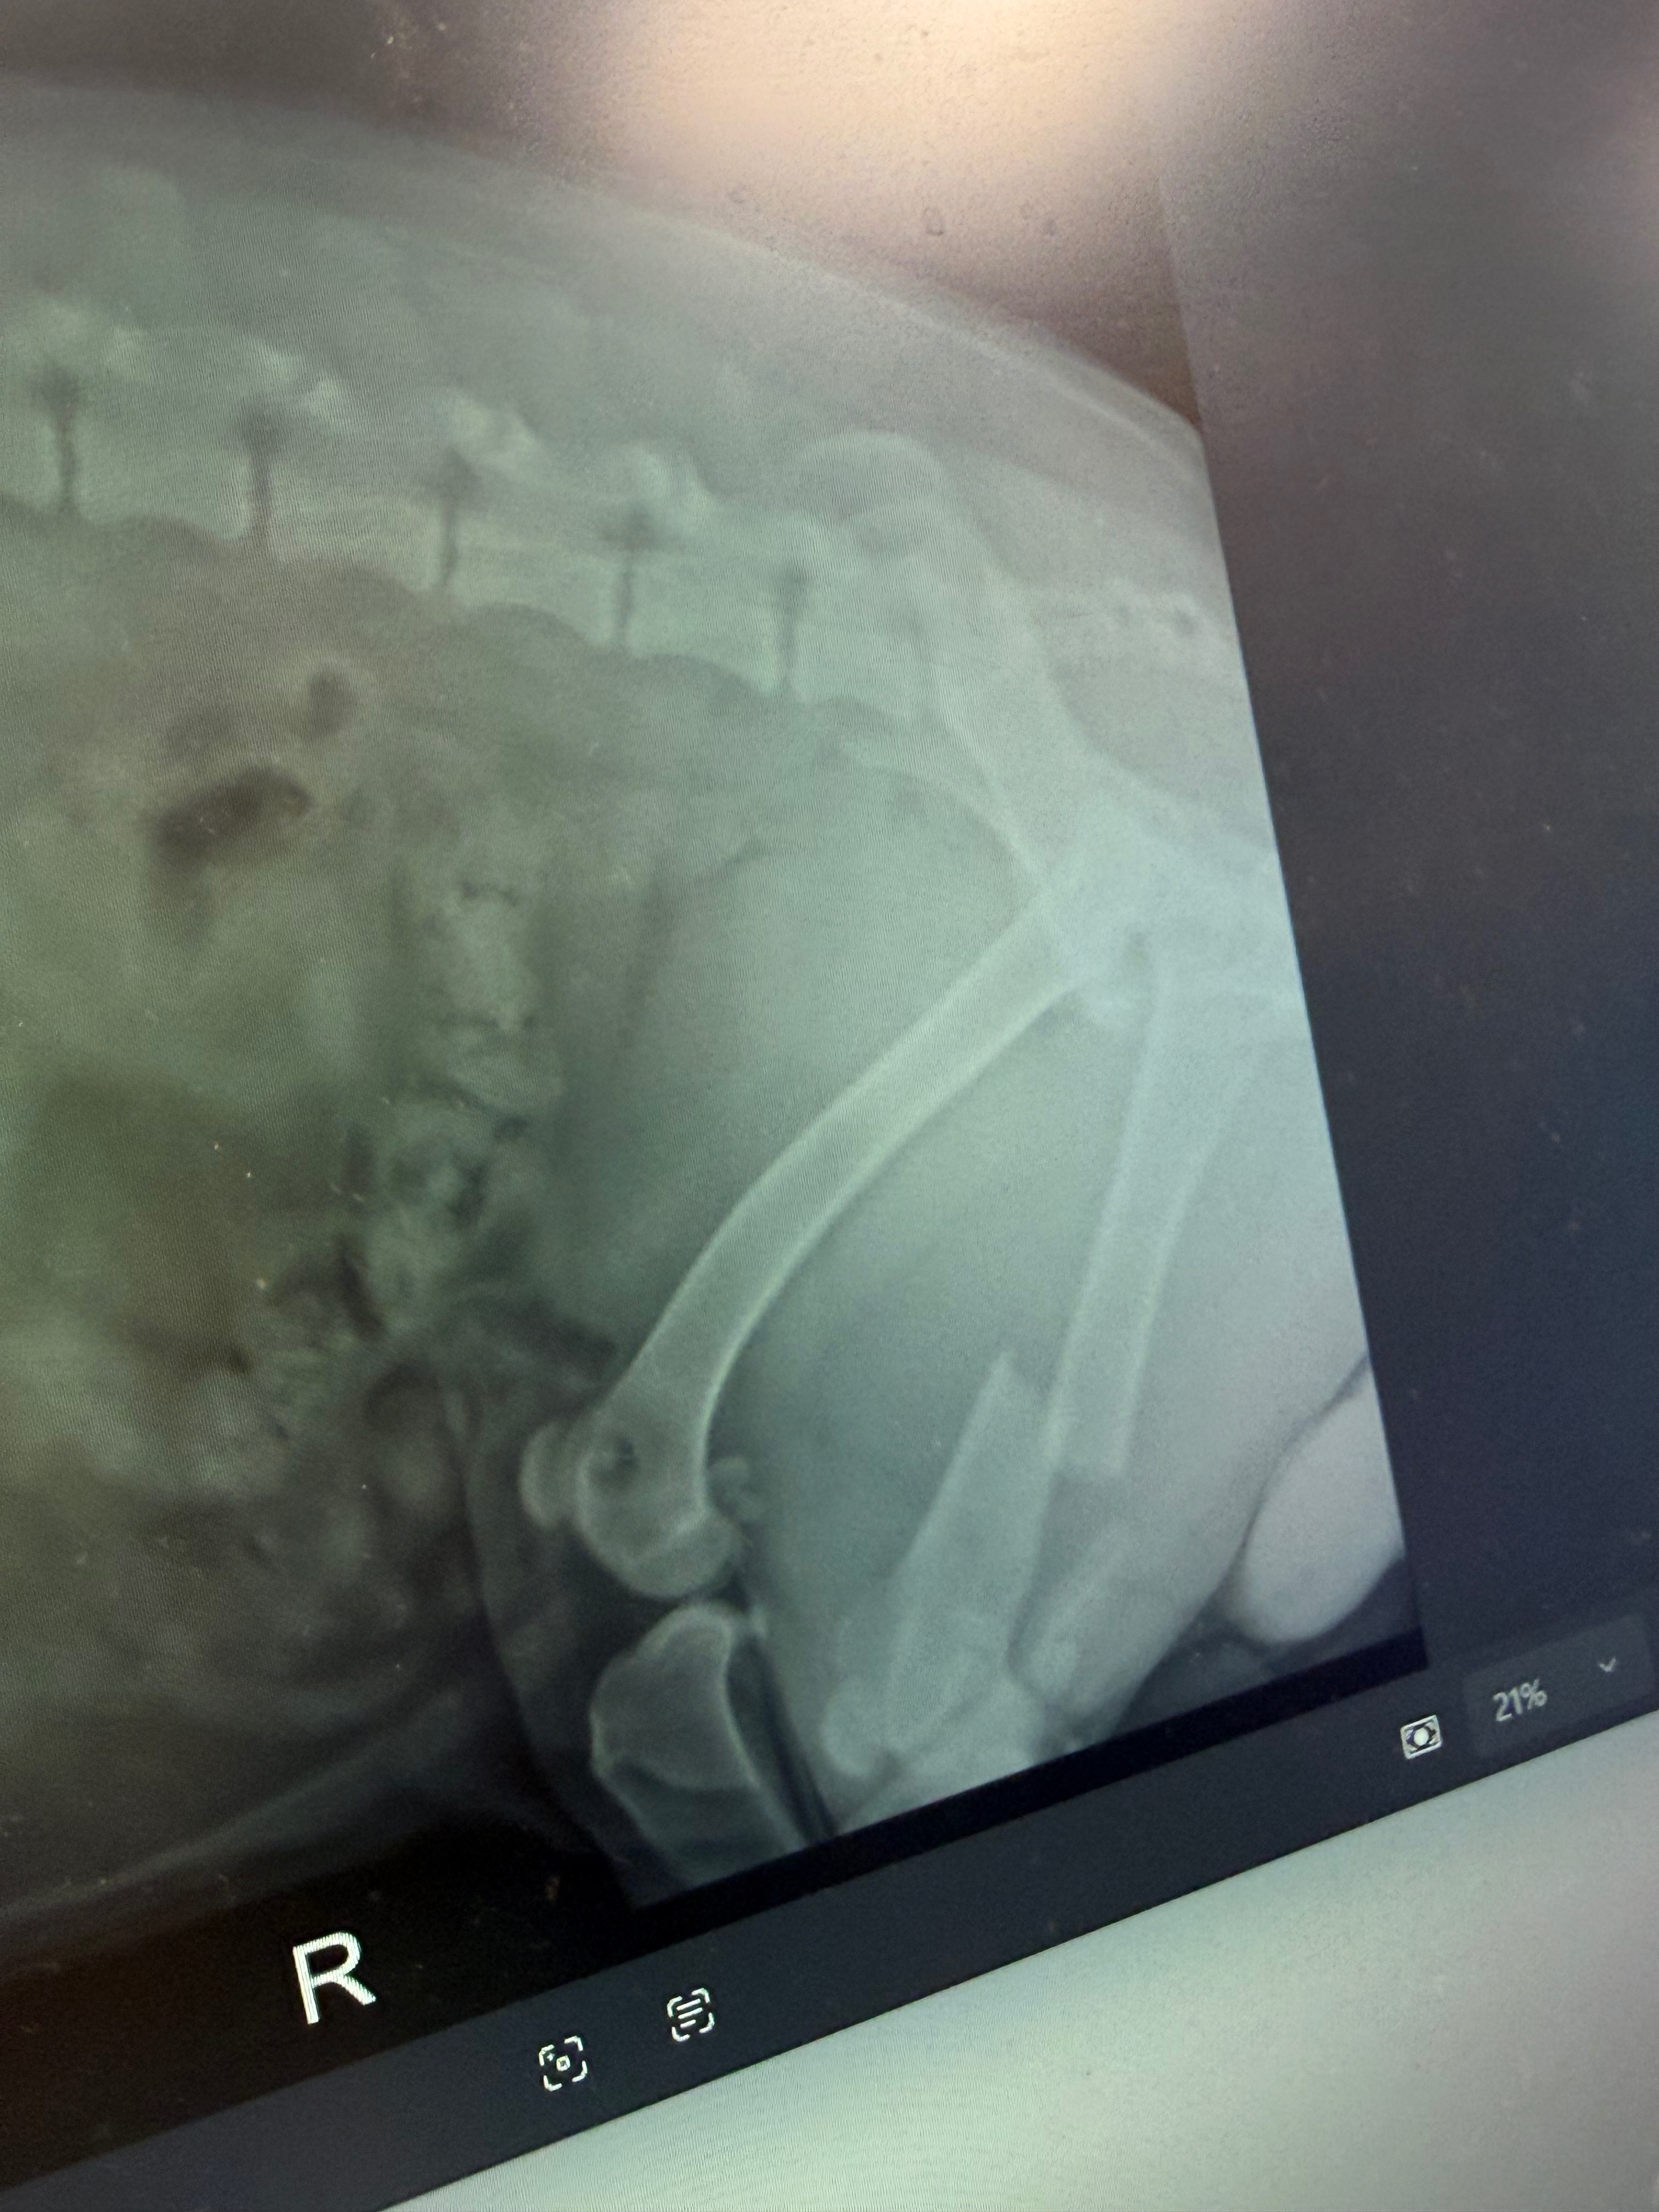

Koda suffered a broken leg, bruised lungs and heart, and several other serious injuries. He is currently on constant oxygen and receiving intensive veterinary care as doctors work tirelessly to stabilize him and give him the best chance at recovery. The road ahead will include surgery, continued hospitalization, medications, and rehabilitation.